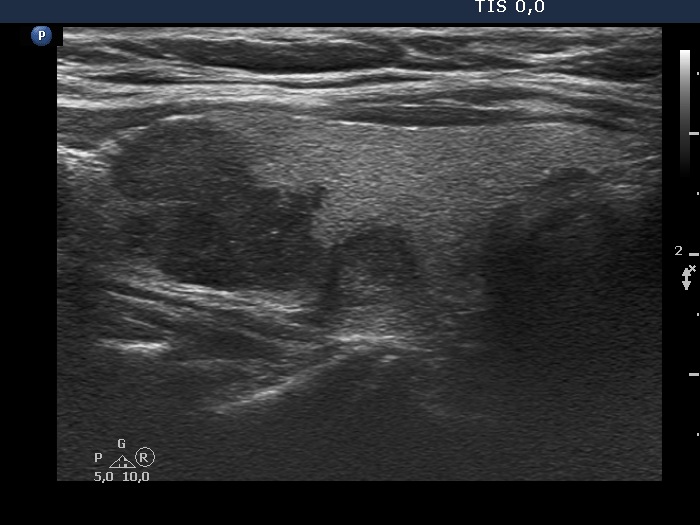

Ultrasonography. The thyroid was echonormal. There were several hypoechogenic nodules in the right lobe. One of the nodules had spiculations. There was a hypoechogenic nodule in the lower part of the right lobe. This lesion presented micro- and macrocalcifications.

Comment. The hypoechoic mass in the right lobe presented undulated margins of non-pathological cause. One of the nodules of this mass had irregular, spiculated borders.